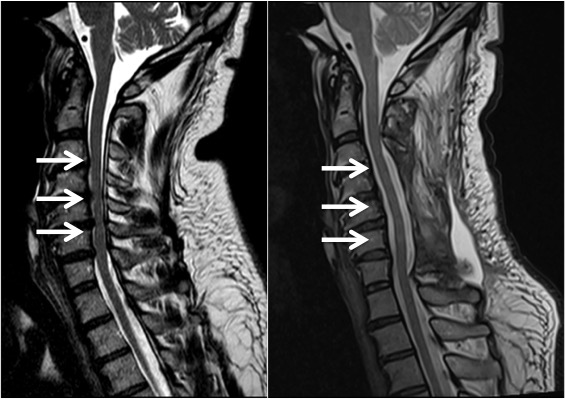

تنگی کانال نخاعی در ناحیه کمری یکی از شایعترین مشکلات ستون فقرات است که میتواند باعث کمردرد، درد پشت، درد ران و زانو شود و زندگی روزمره افراد را تحت تأثیر قرار دهد. این عارضه معمولاً در افراد بالای ۵۰ سال بیشتر دیده میشود، اما عوامل دیگری مانند چاقی، اضافه وزن، چاقی شکمی و حتی […]

تنگی کانال نخاعی: دلایل، علائم و راهحلهای درمانی برای بازگشت به زندگی عادی کانال نخاعی فضایی است درون ستون فقرات که نخاع و اعصاب حیاتی از آن عبور میکنند. در حالت طبیعی، این فضا به اندازه کافی بزرگ است تا نخاع و ریشههای عصبی بتوانند به راحتی فعالیت کنند. اما عواملی مانند افزایش سن، تغییرات […]